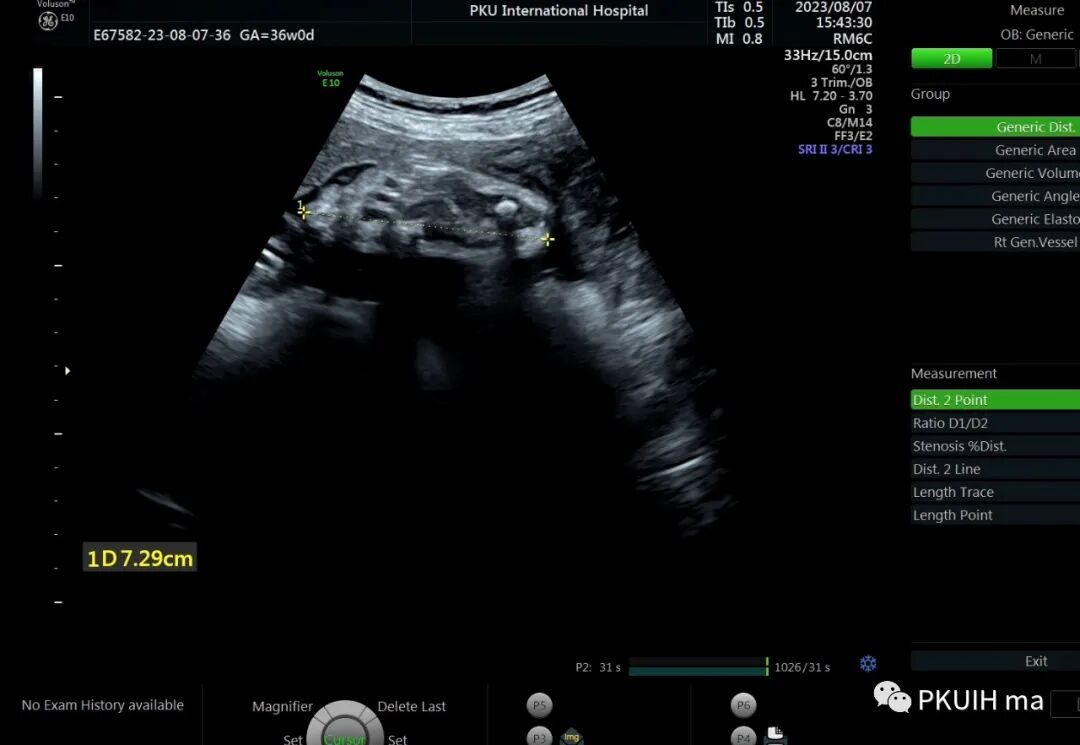

36周检查发现肢体越来越短,股骨和肱骨只相当于25-6周

头围双顶径已经大于相对孕周了,明显的头大肢体短。足底长度正常范围。